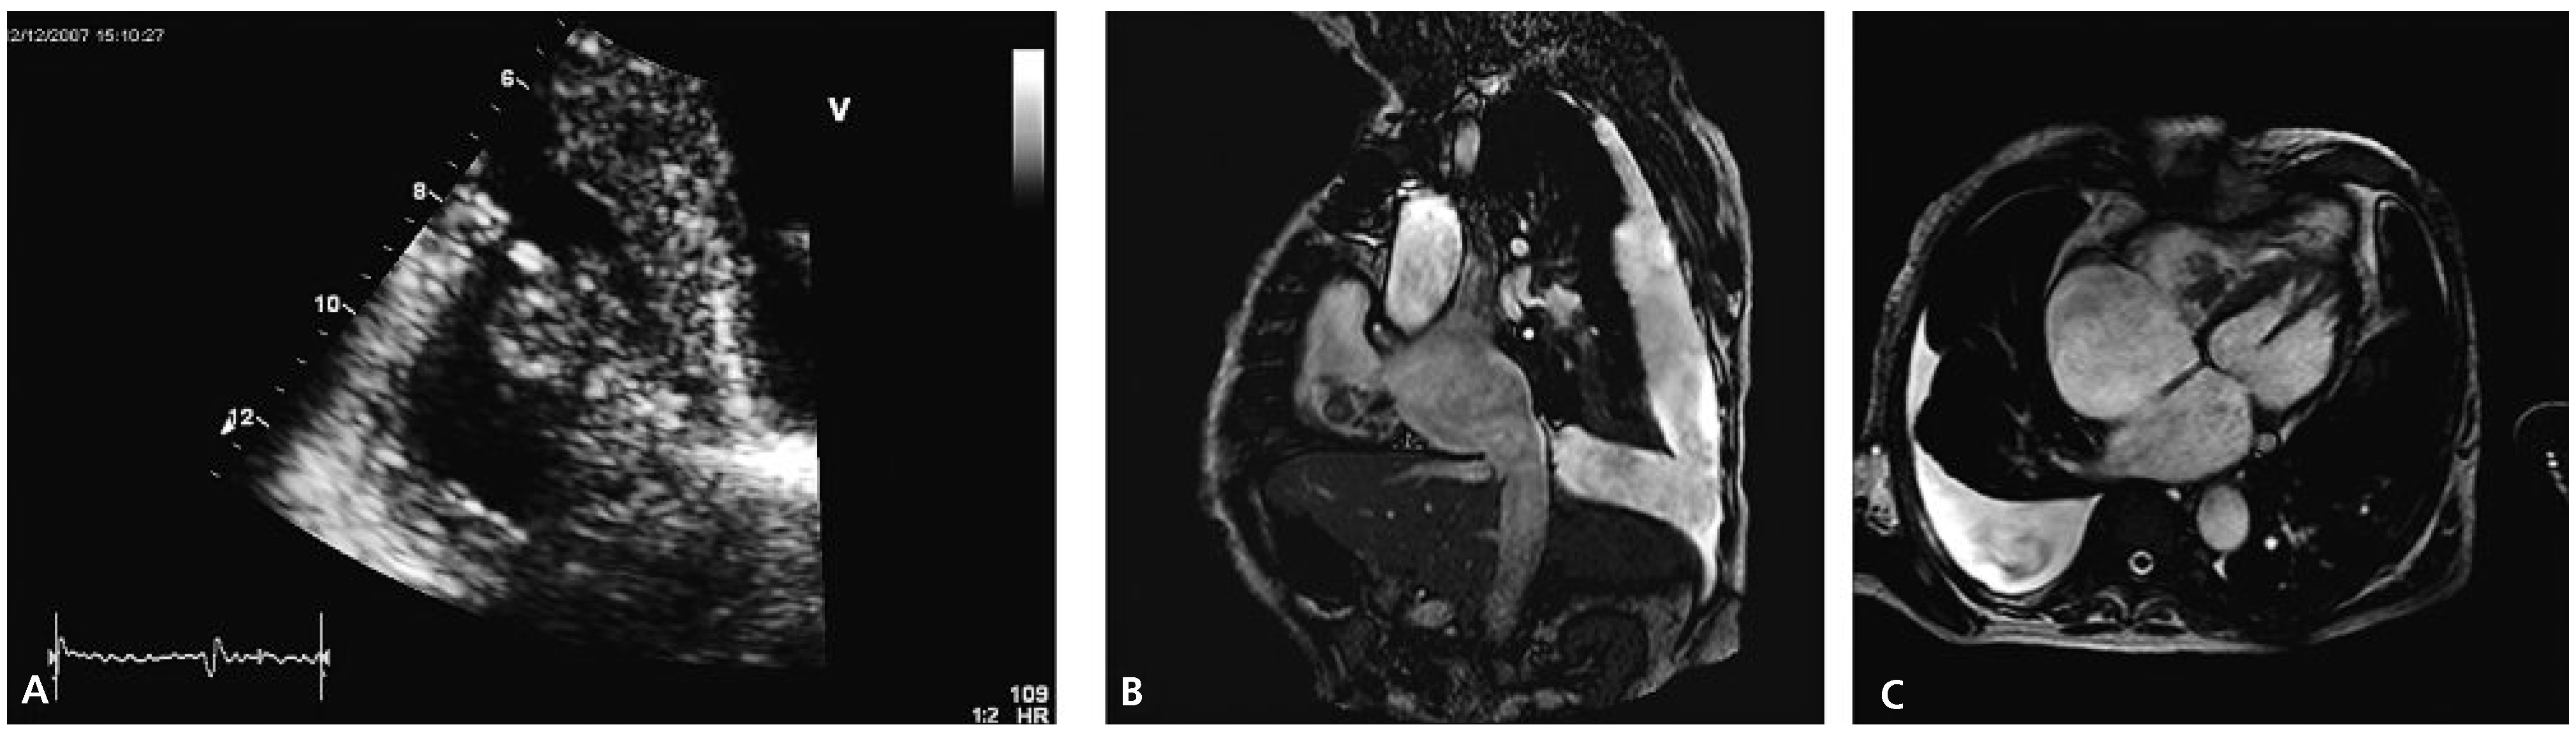

Transthoracic echocardiography revealed concentric left ventricular hypertrophy and a severely reduced global systolic left ventricular function (ejection fraction of 20–25%) due to inferior and posterior akinesia and substantial hypokinesia of the remaining wall segments. Both atria appeared dilated. The right ventricle was visually dilated with marked tricuspid annular dilation (50 mm) and functionally impaired (TAPSE 1.1 cm, TDI 10 cm/s). The aortic and mitral valves were remarkable for severe degenerative signs but besides a slight mitral regurgitation they were functionally normal. Attached to the septal leaflet of the tricuspid valve, an inhomogeneous structure partially prolapsing into the right atrium during systole was found (Figure 1A), associated with visually mild tricuspid valve regurgitation. The pressure gradient across the tricuspid valve was 65 mm Hg suggesting severely elevated systolic pulmonary arterial pressure. A CT scan of the chest confirmed pulmonary emboli in the right main pulmonary artery and in a segmental artery of the left upper lobe.

Figure 1.

(A) Transthoracic echocardiogram showing a right ventricular mass (apical four chamber view). (B,C) Magnetic resonance images demonstrating a right ventricular thrombus.

Cardiac MRI confirmed cardiac thrombus since there was no uptake of contrast agent and no signs suggestive of a tumour (Figure 1B,C). Antibiotics were stopped upon admission. Blood cultures remained negative and the CRP value remained low. Real-time PCR was positive for the V617F mutation of the JAK2-gene making the suspected diagnosis of polycythemia vera (PV) very likely. A bone marrow examination was refused by the patient. Phlebotomy (three times 500 mL) was performed and therapy with hydroxyurea (1000 mg/d) was started. Initially peripheral haematological values were checked daily and following discharge from the hospital they were checked weekly. The anticoagulation was changed to phenprocoumon in order to achieve less variable INR values. Additionally low-molecular weight heparins were applied until stable INR values between 2 and 3 were obtained. Due to the spontaneous intracranial bleeding eleven months earlier, therapy with acetylsalicylic acid was not added.